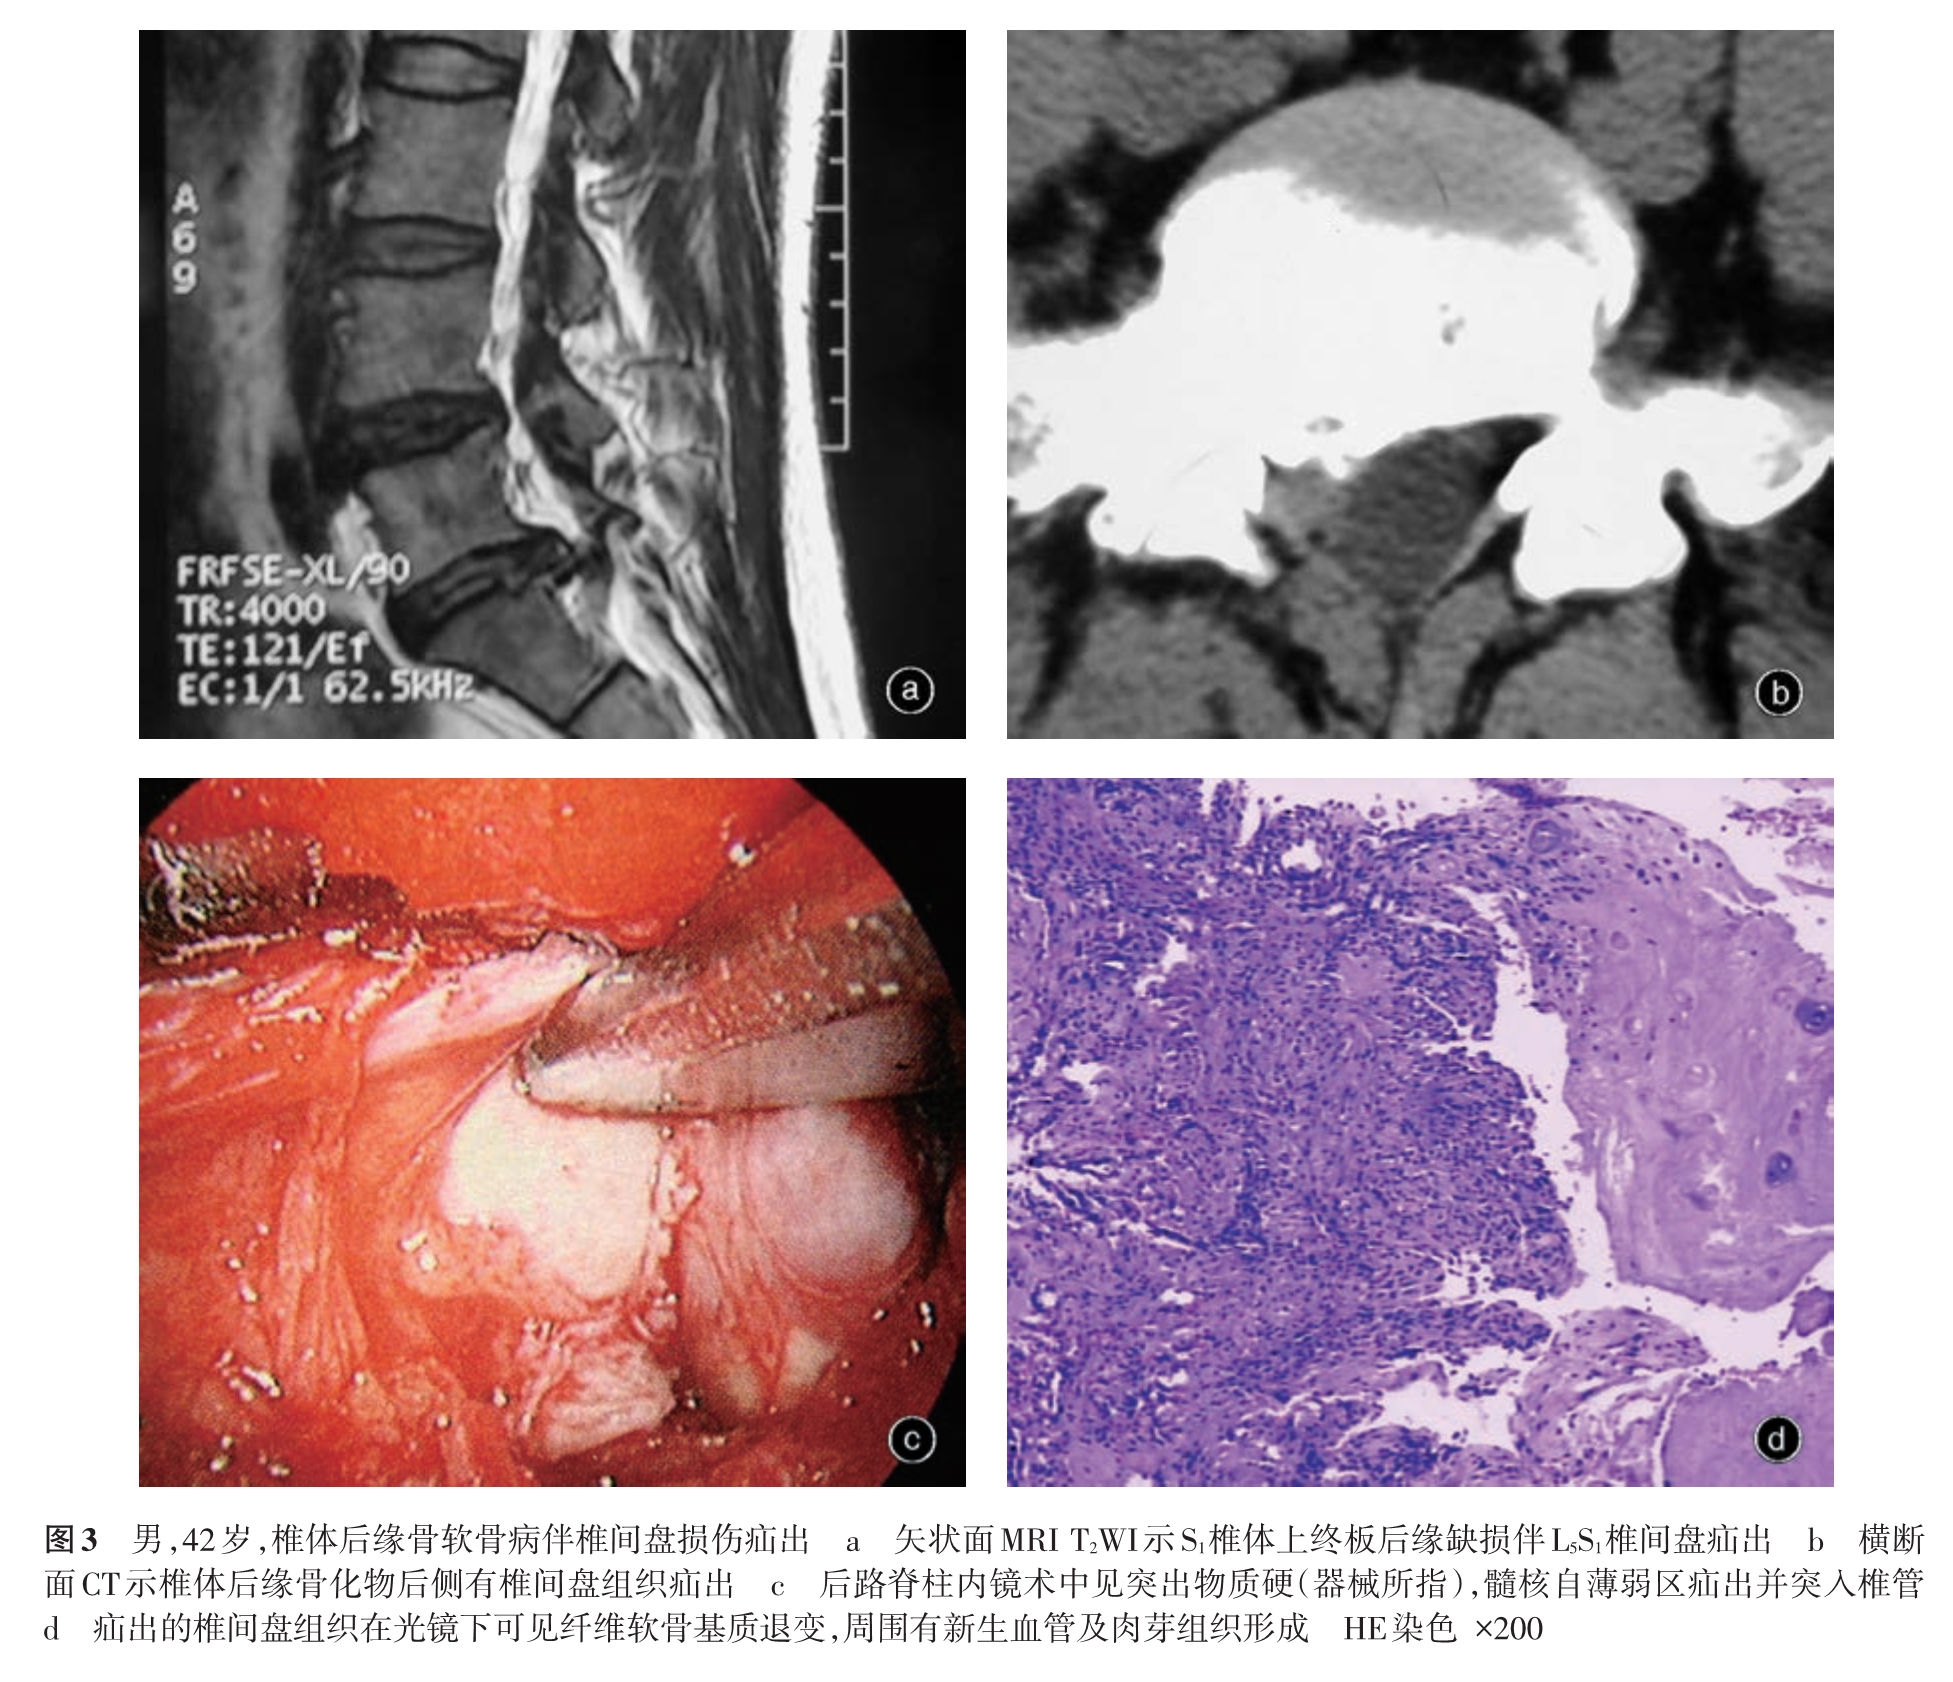

我们在临床实践中发现腰椎间盘突出症在大体病理、免疫学等方面存在较大差异,病变周围组织也有不同的病理改变,存在不同的发病机制,其治疗措施包括手术方法因不同的病理变化而有所差异。基于以上认识,我们在以往分类方法的基础上提出一种新的腰椎间盘突出症病理学分型,分为损伤疝出型、退变突出型、椎体后缘骨软骨病伴椎间盘突出和椎间盘囊肿四型[5-11],并建议根据不同的病理类型进行临床评估,包括手术方法的选择。